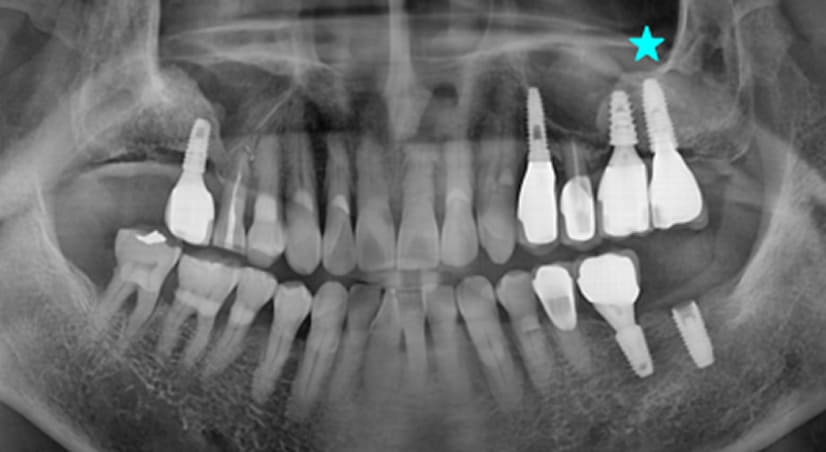

13+ 年

-

种植体植入 2012年10月 -

最终修复体 2013年1月 -

随访:13年 2025年3月